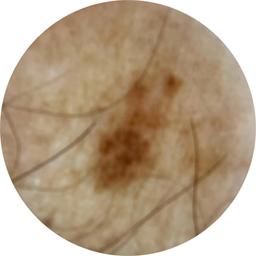

ISIC_4173539

acquisition_day 133

age_approx 65

anatom_site_1 Upper extremity

anatom_site_general upper extremity

diagnosis_1 Benign

diagnosis_confirm_type single image expert consensus

fitzpatrick_skin_type I

image_type dermoscopic

personal_hx_mm True

sex male